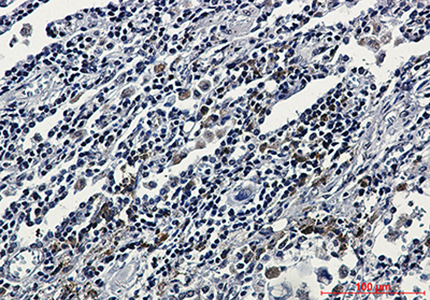

WB,IHC-P,IP

WB: 1:500-1:1000 IHC: 1:50-1:100 IP: 1:20